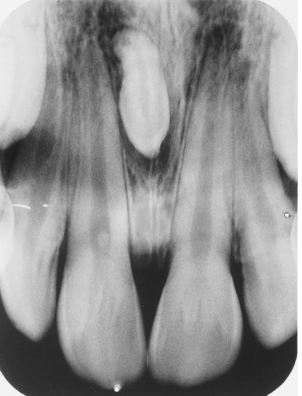

In this image you can see the two central incisors and a single lateral incisor. Clinically, there was a notch in the midincisal area. The anomaly here is

gemination

fusion

twinning

microdontia

Study the lateral incisor. What feature(s) can you not regarding this tooth?

accessory lingual cusp

dens in dente

dilacerated crown

peg lateral

all of the above